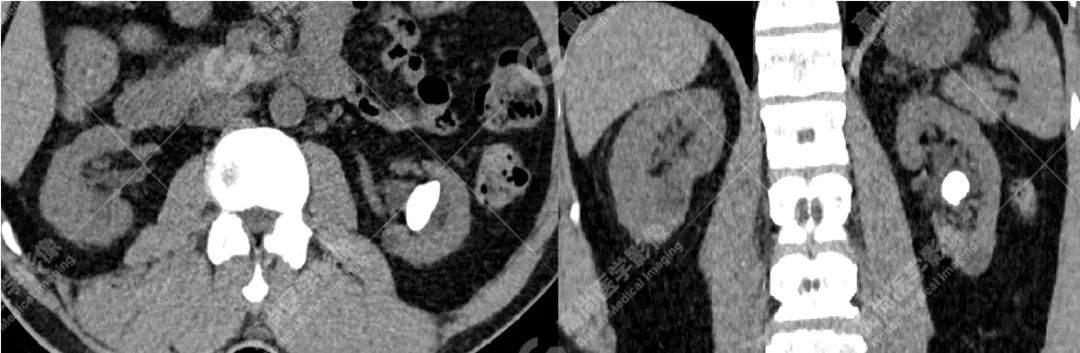

病例一

病史摘要

患者左肾结石,双能量 CT 结石分析示其主要成分为羟磷灰石。

CT 平扫因其安全性和高度敏感性已成为评估泌尿系结石的标准检查方法。而双源 CT(dual-source computed tomography,DSCT)在一次扫描过程中能够同时进行低能量和高能量扫描,使其拥有能够对电子密度相同但光子吸收能力不同的结石进行鉴别的能力。

计算感兴趣区结石在低能量和高能量原位扫描下的衰减值比值(AR 值),与体外结石的已知化学成分的 AR 值进行对比,因此得到体内结石的化学成分。(此步骤在工作站进行,如上成分标识图)